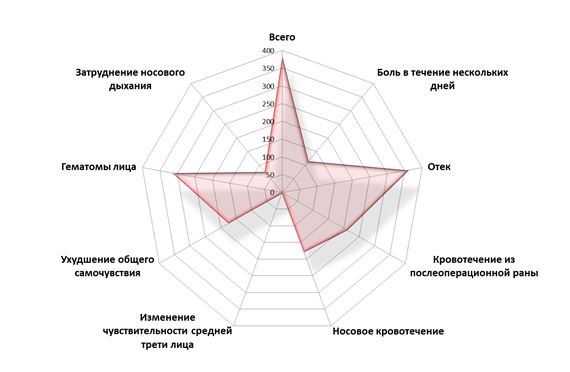

В среднем, реабилитационный период после операции синуслифтинга занимает 3-7 дней, в зависимости от методики и объемов оперативного вмешательства. Вопреки распространенному мнению, болезненность не является преобладающим послеоперационным симптомом, наиболее часто мы сталкиваемся с отеком области операции, гематомами и кровотечением (рисунок 63):

Окончанием реабилитационного периода является отсутствие дискомфорта в области послеоперационной раны и возвращение пациента к привычному образу жизни. До этого момента пациент нуждается в обязательном наблюдении лечащего доктора.